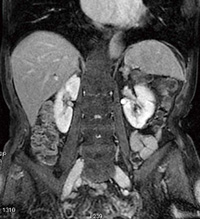

また,2008年に入ってバイエル薬品社より発売されたMRI用肝臓造影剤「EOB・プリモビスト」を用いた検査においても,非常に良好なコントラストが得られている(図5)。

図5 EOB静注時のLAVA画像:HCC症例(画像ご提供:市立旭川病院様)